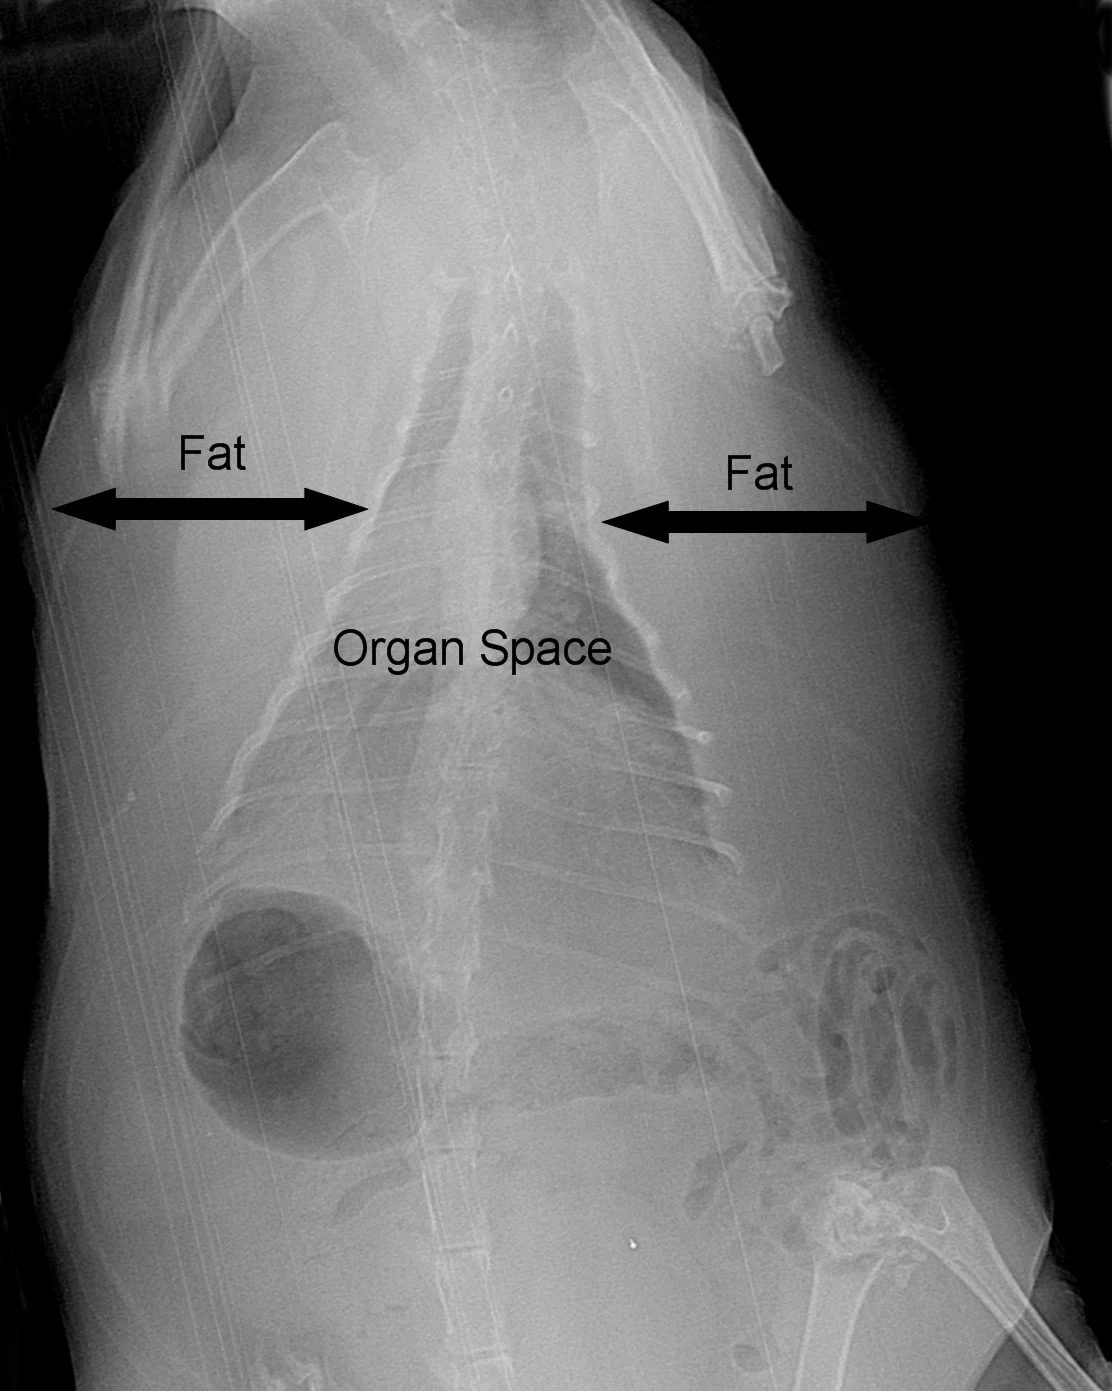

Examples